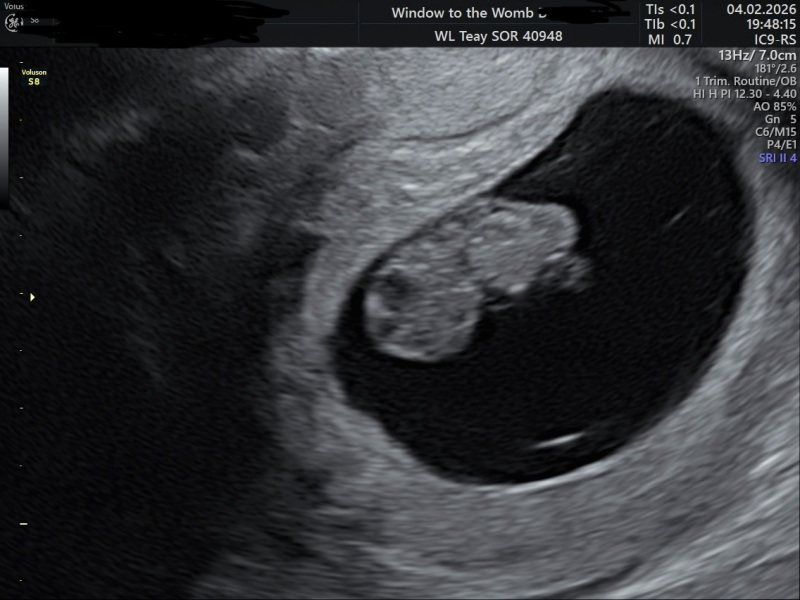

Just thought I’d check in and let you all know I had my early reassurance scan and here is little bean measuring 8w5d with a strong heartbeat and a due date of 11th September ā¤ļø I feel unbelievably lucky to have been blessed with this pregnancy šŸ™šŸ¼